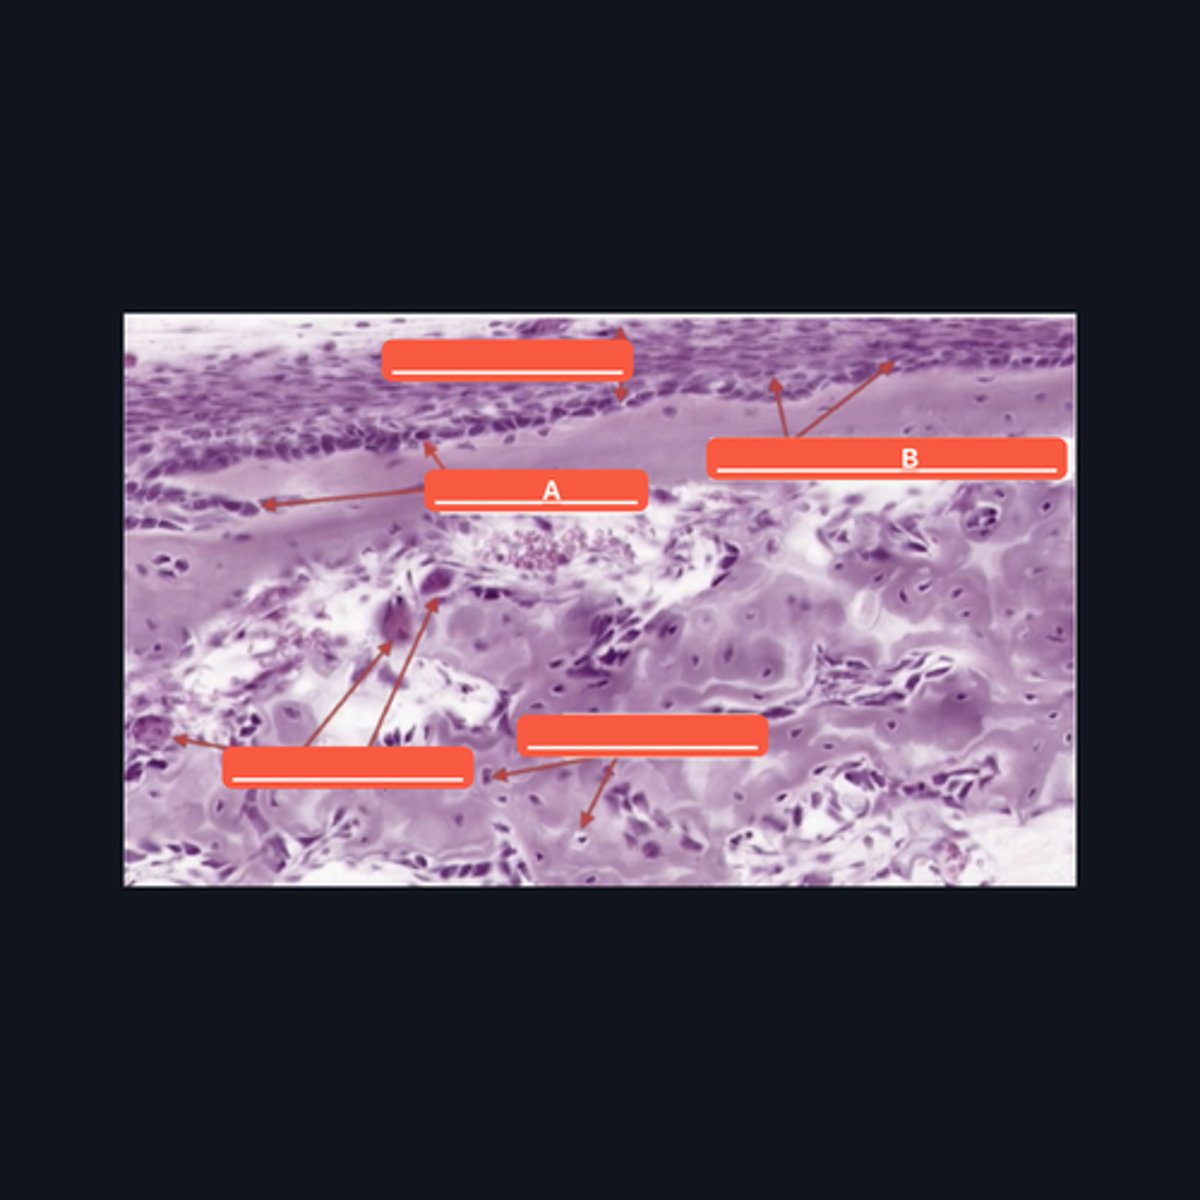

Fibrocartilage; intervertebral disc, articular disc, glenoid and acetabular labra

What type of cartilage is in the image? Where is this specific type of cartilage found?

Collagen fibers

This type of cartilage is abundant in what fibers?

Dense regular connective tissue; chondrocytes; lacunae

This cartilage is commonly mistaken as _____. However, when examined closely, _____are contained in _____ (identify pointed structures), making it a cartilage.